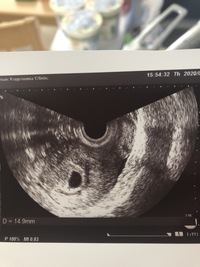

妊娠5週-妊娠5週・6週の「中絶手術について」 「初期中絶手術」とは妊娠11週6日まで (妊娠12週未満)に行う中絶手術のことです。 「中期中絶手術」とは妊娠12週~妊娠21週6日の間 (妊娠22週未満)に行う中絶手術のことです。妊娠5週前半 リングがみえはじめる まず胎嚢の中にはリング(卵黄嚢)が見え始めます。このころの卵黄嚢は正円です。胎芽はそのどこかにいるはずですが、まだ超音波でその存在を確認できません。 妊娠5週後半から6週前半 リングに輝くダイヤが膨らむ

5 産科一般超音波検査 初期編 正常所見4 7週 日本産婦人科医会

超音波写真館 妊娠初期4 7週 超音波教室 ママニティ大百科